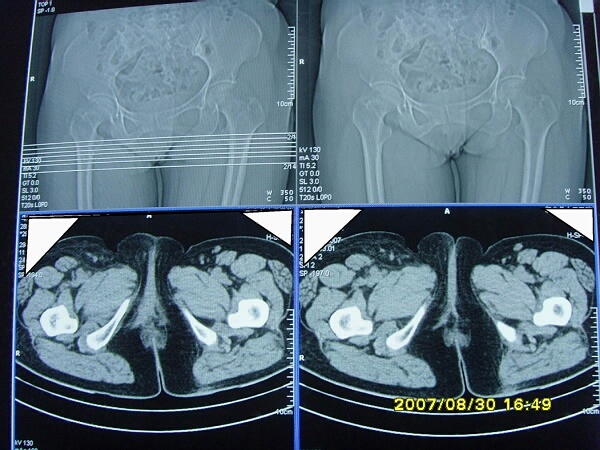

以下是引用zjzjr在2007-9-11 22:21:00的发言:[br]右侧股骨上段前部皮下可见不椭圆形软组织密度影,增强呈环形强化,周围皮下脂肪混浊,考虑感染性病变,不知临床症状如何.